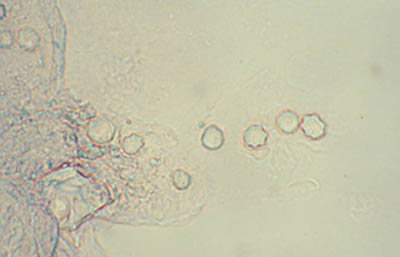

Frotis - extendido en capa

Preparaciones de extendido en capa sobre laminilla con agua destilada sin colorear, en campo claro y bajo contraste de fases: permite buena visualización de las formas Quísticas de Acanthamoeba

Magnificación 160x